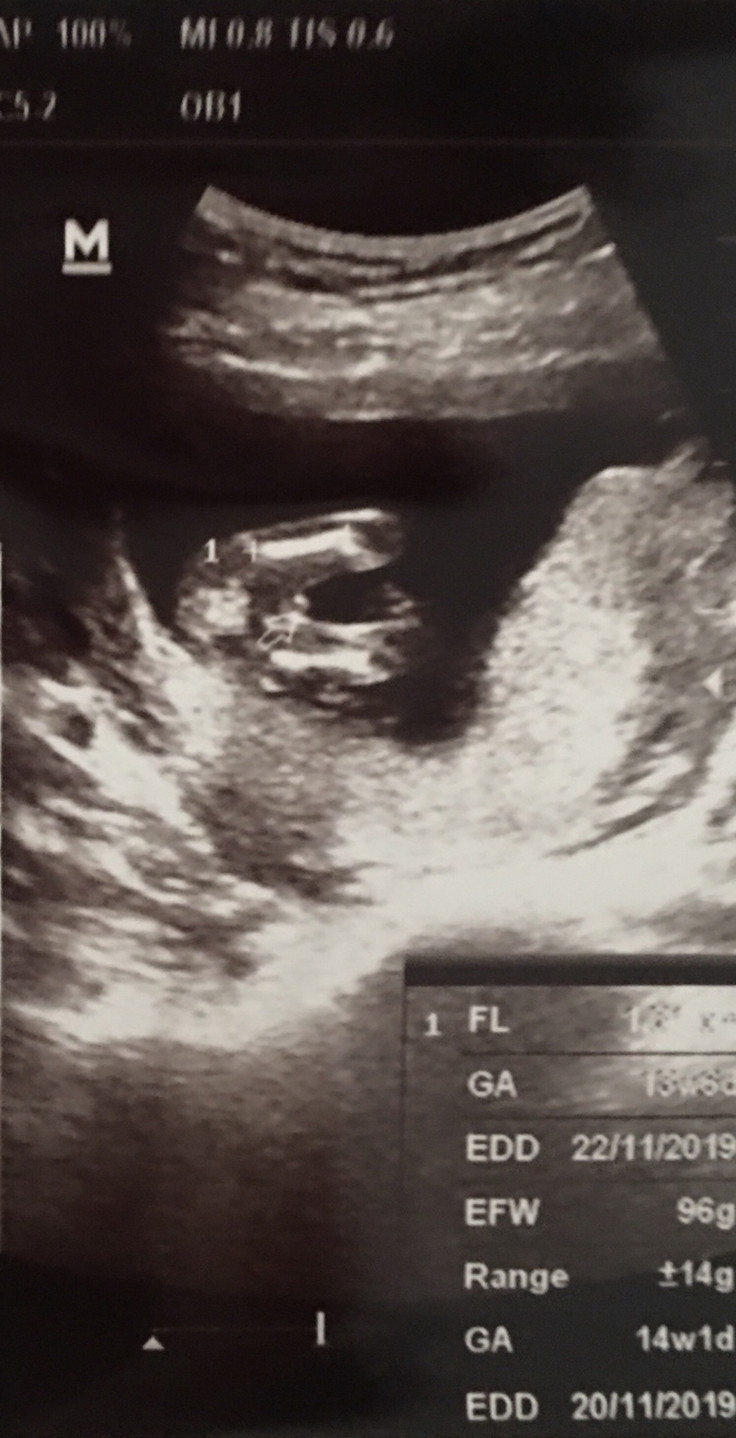

เจอตอน 14 วีคค่าาา ผู้ชายค่ะ^^